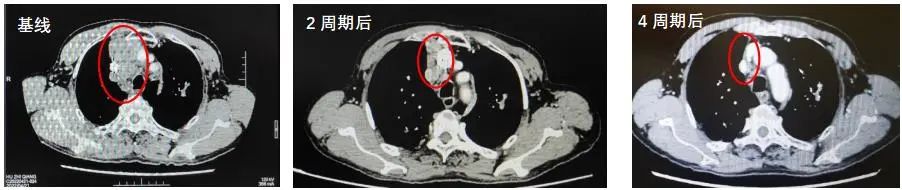

2022年5月11日-2022年7月30日:PD-1*制剂抑**+EC方案化疗共4周期,具体方案为:斯鲁利单抗(250mg,4.5mg/kg)+依托泊苷(0.16g d1-3)+卡铂(0.53g AUC5)。

2022年7月4日复查CT:与PACS20220421老片对比,现片示:1.右肺上叶前段不规则肿块灶(40mm×37mm)并纵隔多发肿大淋巴结明显缩小,上腔静脉受压变扁较前减轻:考虑周围型肺CA并纵隔淋巴结转移。2.双上肺、左下肺肺结核可能性大,CT表现为稳定性征象。3.慢性支气管疾患:肺气肿;肺大泡。

总体疗效评价为PR。

2022年8月23日复查CT:1.右肺上叶前段不规则肿块灶(40mm×36mm)并纵隔多发肿大淋巴结基本同前,上腔静脉受压变扁同前。2.双上肺、左下肺肺结核可能性大,CT表现为稳定性征象。3.慢性支气管疾患:肺气肿;肺大泡,基本同前。4.升主动脉扩张。

疗效维持PR。